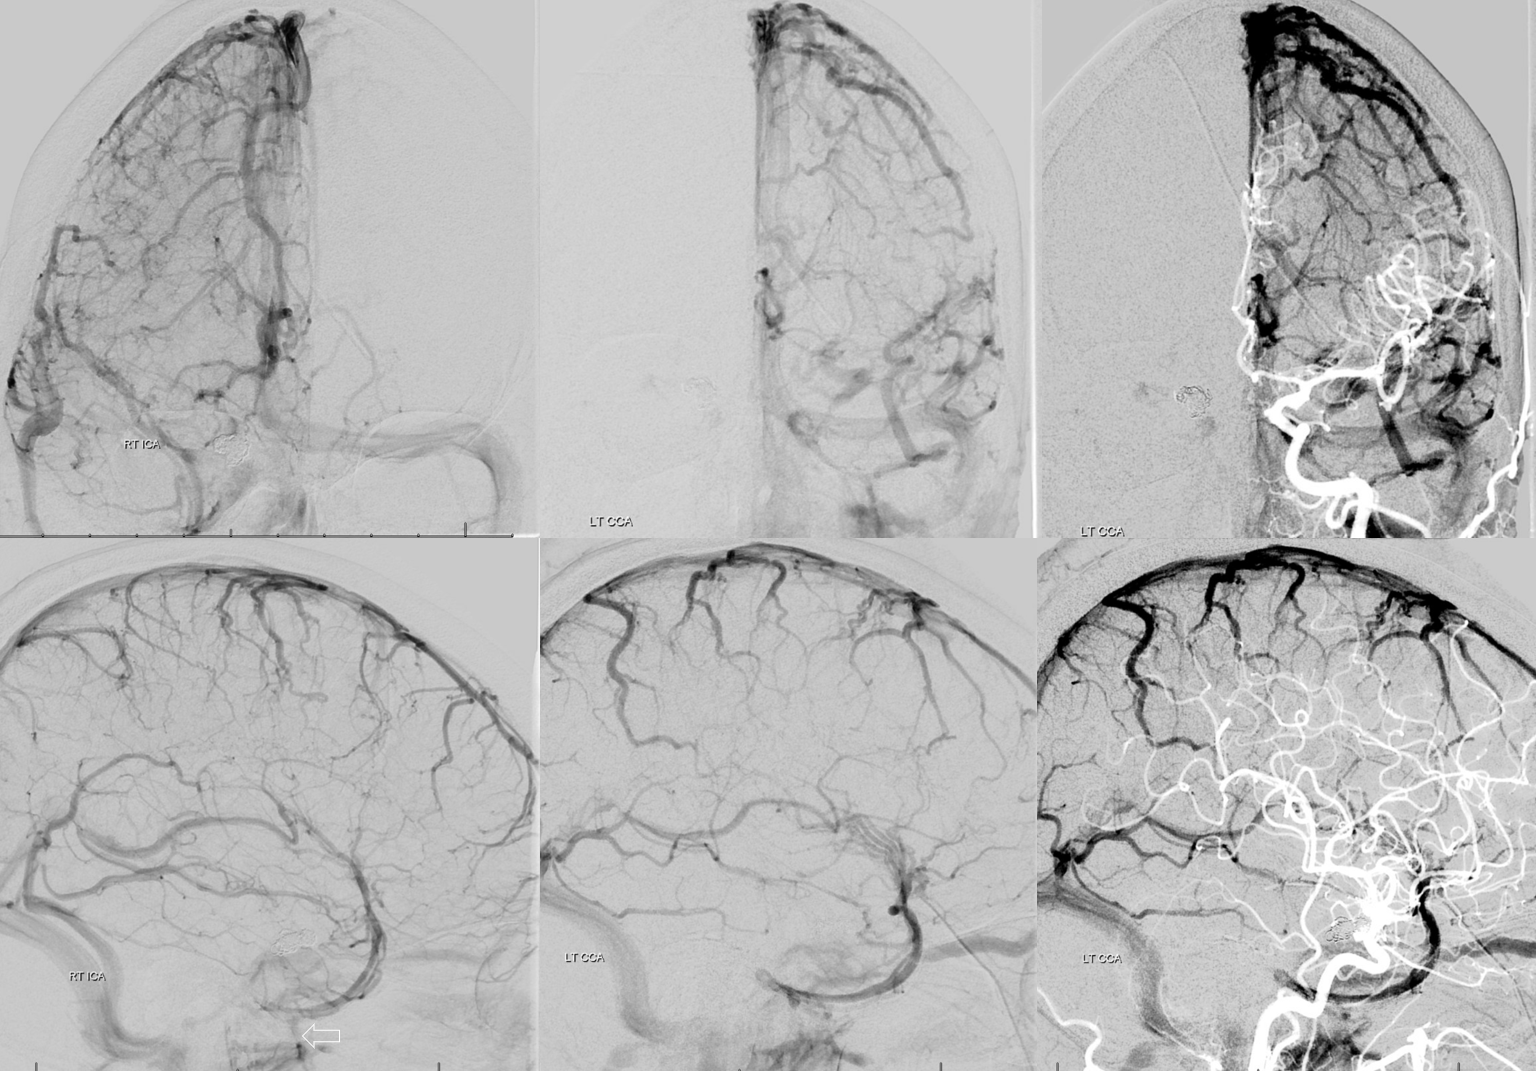

Following embolization, resection, recurrence (as frequently the case with childhood AVMs) and gamma-knife, things look good. Stereo, of course.

Following embolization, resection, recurrence (as frequently the case with childhood AVMs) and gamma-knife, things look good. Stereo, of course.